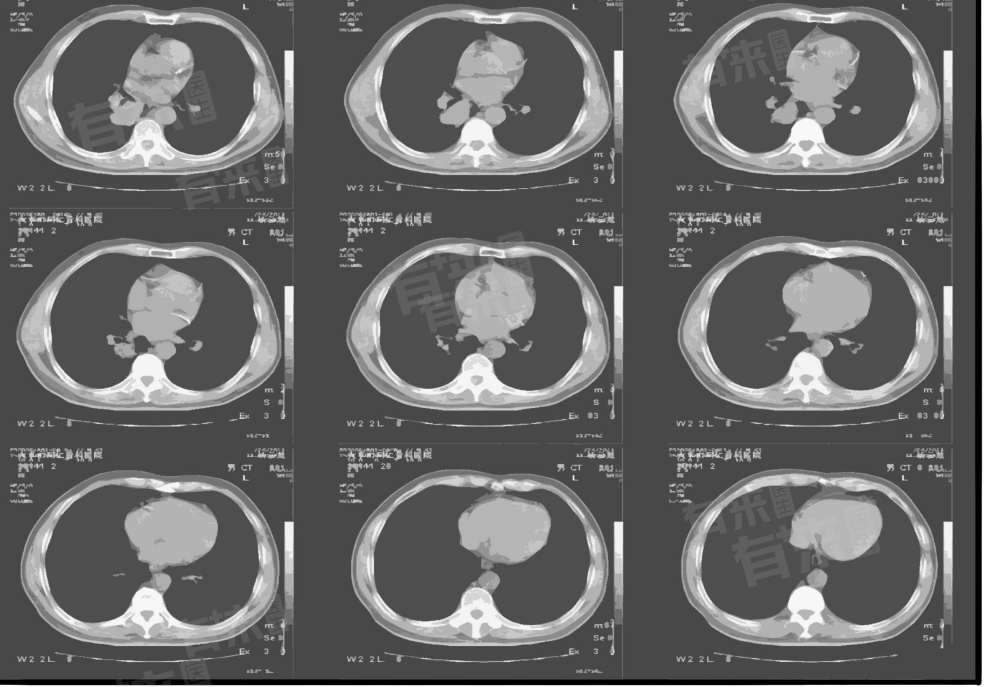

胸部CT平扫可检查肺部及胸膜内脏器、胸部骨性组织、纵隔及内部组织、心脏等部位,还能涵盖其他相关结构,为多种疾病诊断提供依据。

- 胸部CT平扫能够清晰地显示肺部结构,包括肺纹理、支气管、肺动脉等。可以初步判断这些部位是否存在损伤、炎症、感染、肿瘤等病理变化。也能观察胸膜及其内脏器,如气管、支气管等的情况。

- 纵隔是胸腔内的一个重要区域,包含了许多重要的组织和器官。胸部CT平扫能够筛查纵隔内的肿瘤,如淋巴瘤、胸腺瘤、食管肿瘤、神经瘤等。同时,它还能观察纵隔内血管、胸腺、胸椎等的情况。

- CT平扫不仅可以显示心脏的大小和形态,还能排查有无心包积液等心脏疾病,还能观察心脏的主动脉的形态。

通过胸部CT平扫,可以获得高分辨率的胸部图像,帮助诊断各种疾病,制定治疗方案,评估疾病的严重程度和治疗效果。进行胸部CT平扫前应向医生提供详细的病史和症状,便于更好地解读检查结果。患者也应了解胸部CT平扫的注意事项,如禁食、去除金属物品等,确保检查的准确性和安全性。